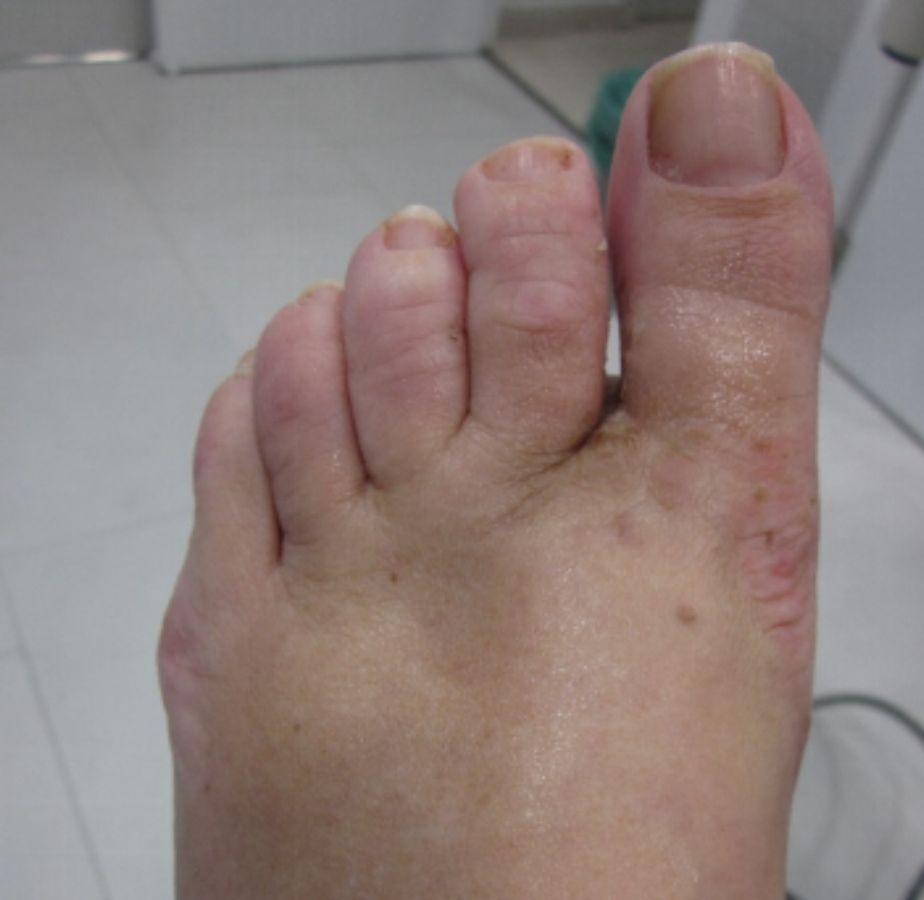

ANTES

casos reales juanetes alicante (4)